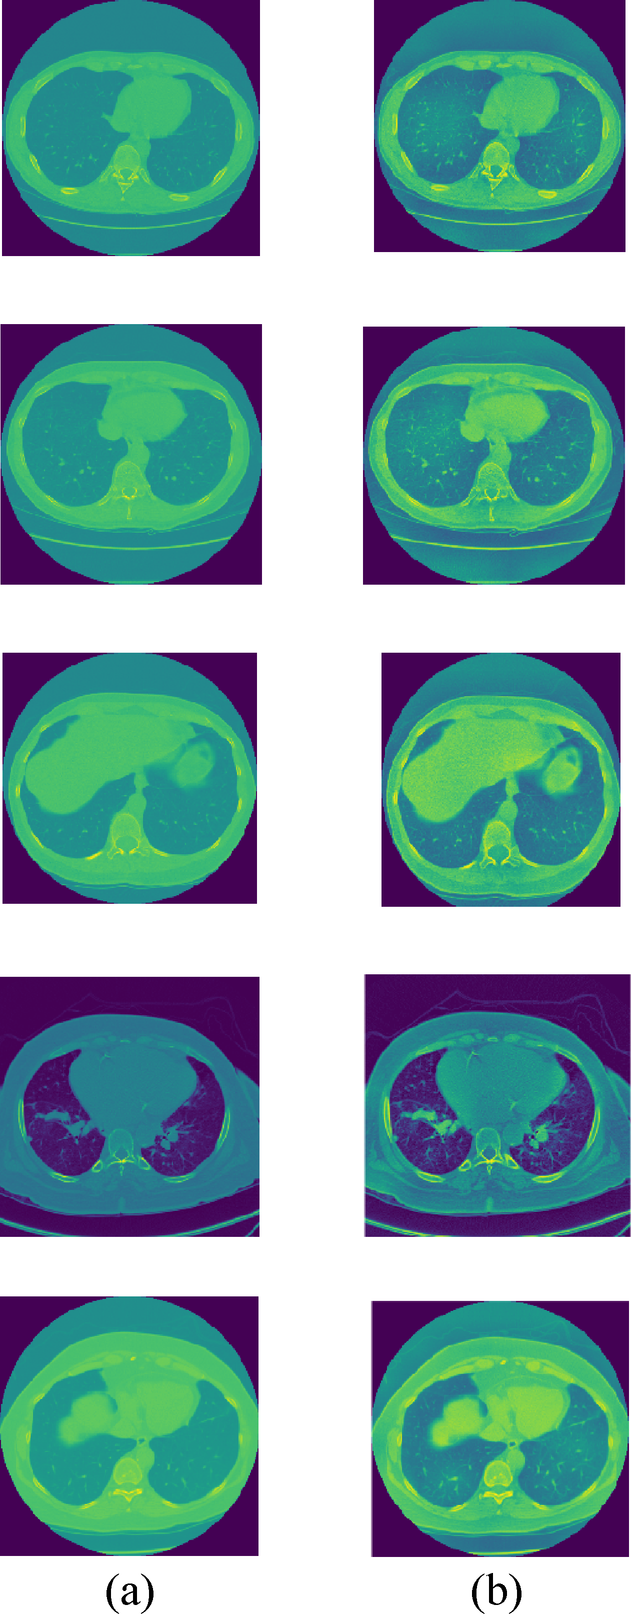

Performance analysis

Pre-processed outcomes (a) Sample Images and (b) HE utilizing pre-processed images.